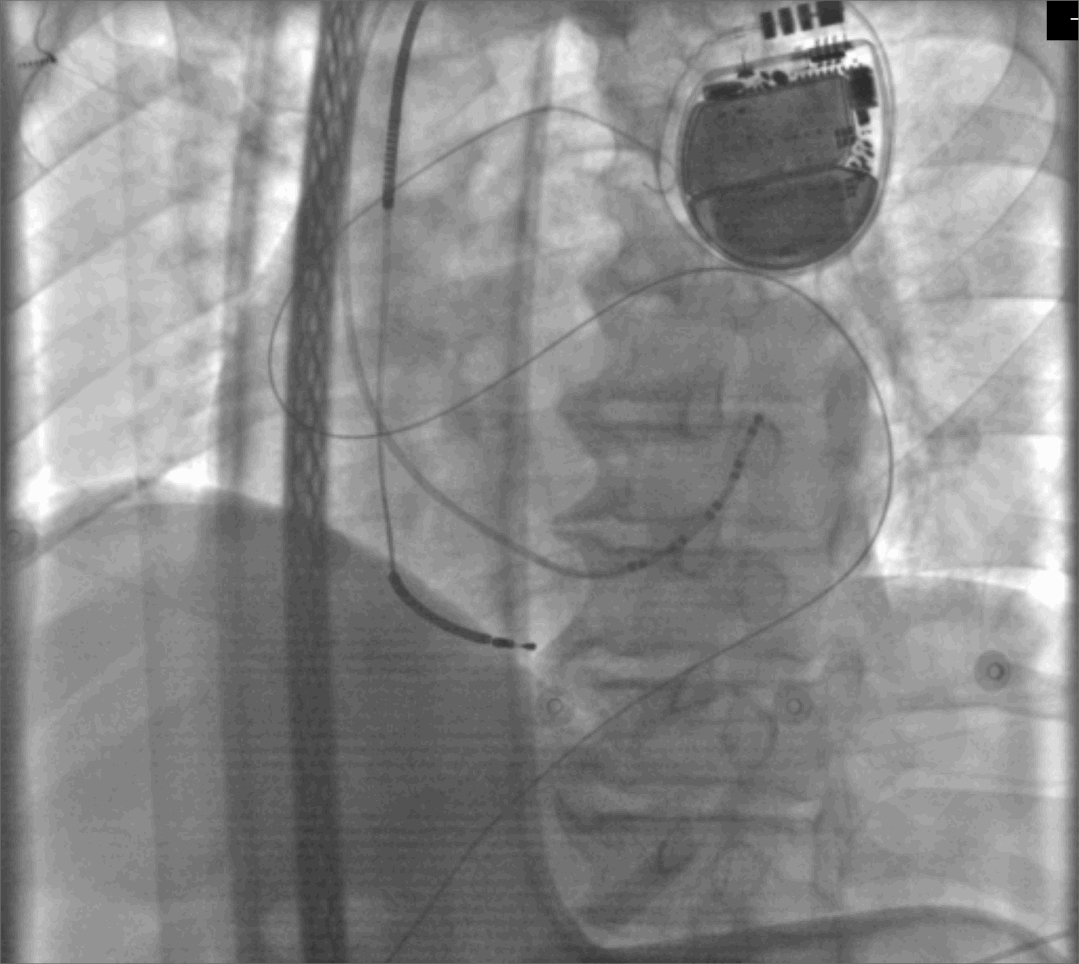

手术于10月12日上午在心脏介入中心实施。为保障患者术中安全,麻醉科对患者进行气管插管、有创机械通气,并进行全身麻醉。心内科电生理团队迅速完成经剑突下途径干性心包穿刺后,心内科ECMO团队在血管外科的积极配合和保障下顺利完成ECMO动、静脉插管和ECMO的运行,运行过程中患者生命体征稳定,ECMO运行状态良好。

图片

经剑突下途径干性心包穿刺